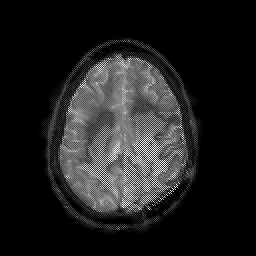

Glioblastoma multiforme overlay -- Slice #38

[Home][Help][Clinical][Tour 1][Tour 2][Tour 3] Slice 38